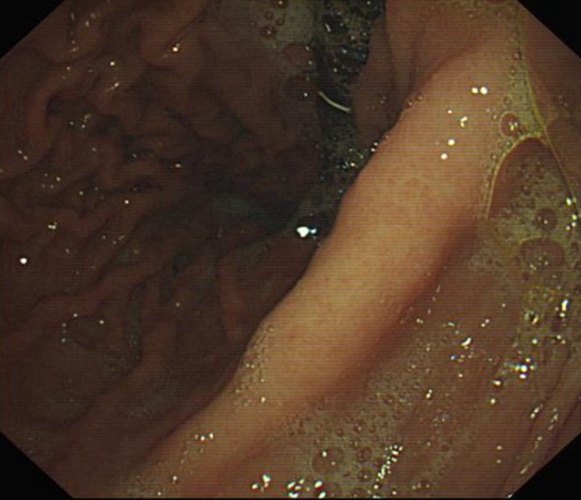

急性胃炎圖片

急性胃炎

急性胃炎胃部